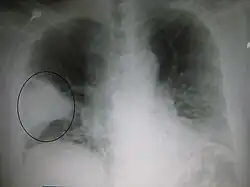

Right upper lobe pneumonia as marked by the circle. -

The discovery of x-rays made it possible to determine the anatomic type of pneumonia without direct examination of the lungs at autopsy and led to the development of a radiological classification. Early investigators distinguished between typical lobar pneumonia and atypical (e.g. Chlamydophila) or viral pneumonia using the location, distribution, and appearance of the opacities they saw on chest x-rays. Certain x-ray findings can be used to help predict the course of illness, although it is not possible to clearly determine the microbiologic cause of a pneumonia with x-rays alone.

AP CXR showing left lower lobe pneumonia associated with a small left sided pleural effusion -

AP CXR showing right lower lobe pneumonia -

AP CXR showing pneumonia of the lingula of the left lung -

Left upper lobe pneumonia with a small pleural effusion.

Right lower lobe pneumonia as seen on a lateral CXR